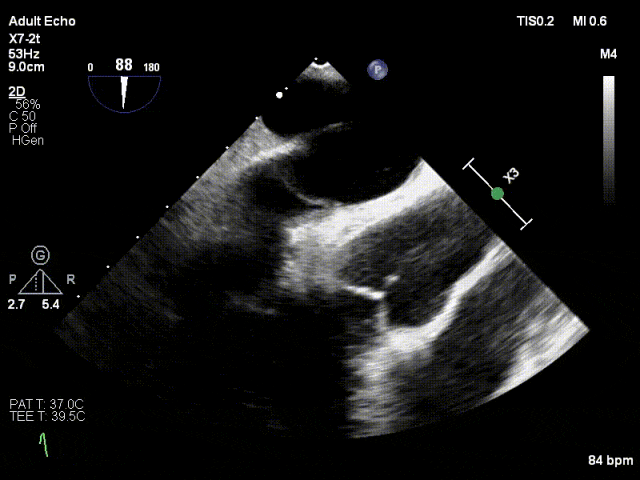

术中

TTE下捕捞瓣叶

瓣叶捕获,Bouncing明显

缓慢关闭夹合角度至30°

TTE上彩评估无明显反流

关闭瓣膜夹

L侧残余微量功能性反流

TMPG:1mmHg

肺静脉逆流消失